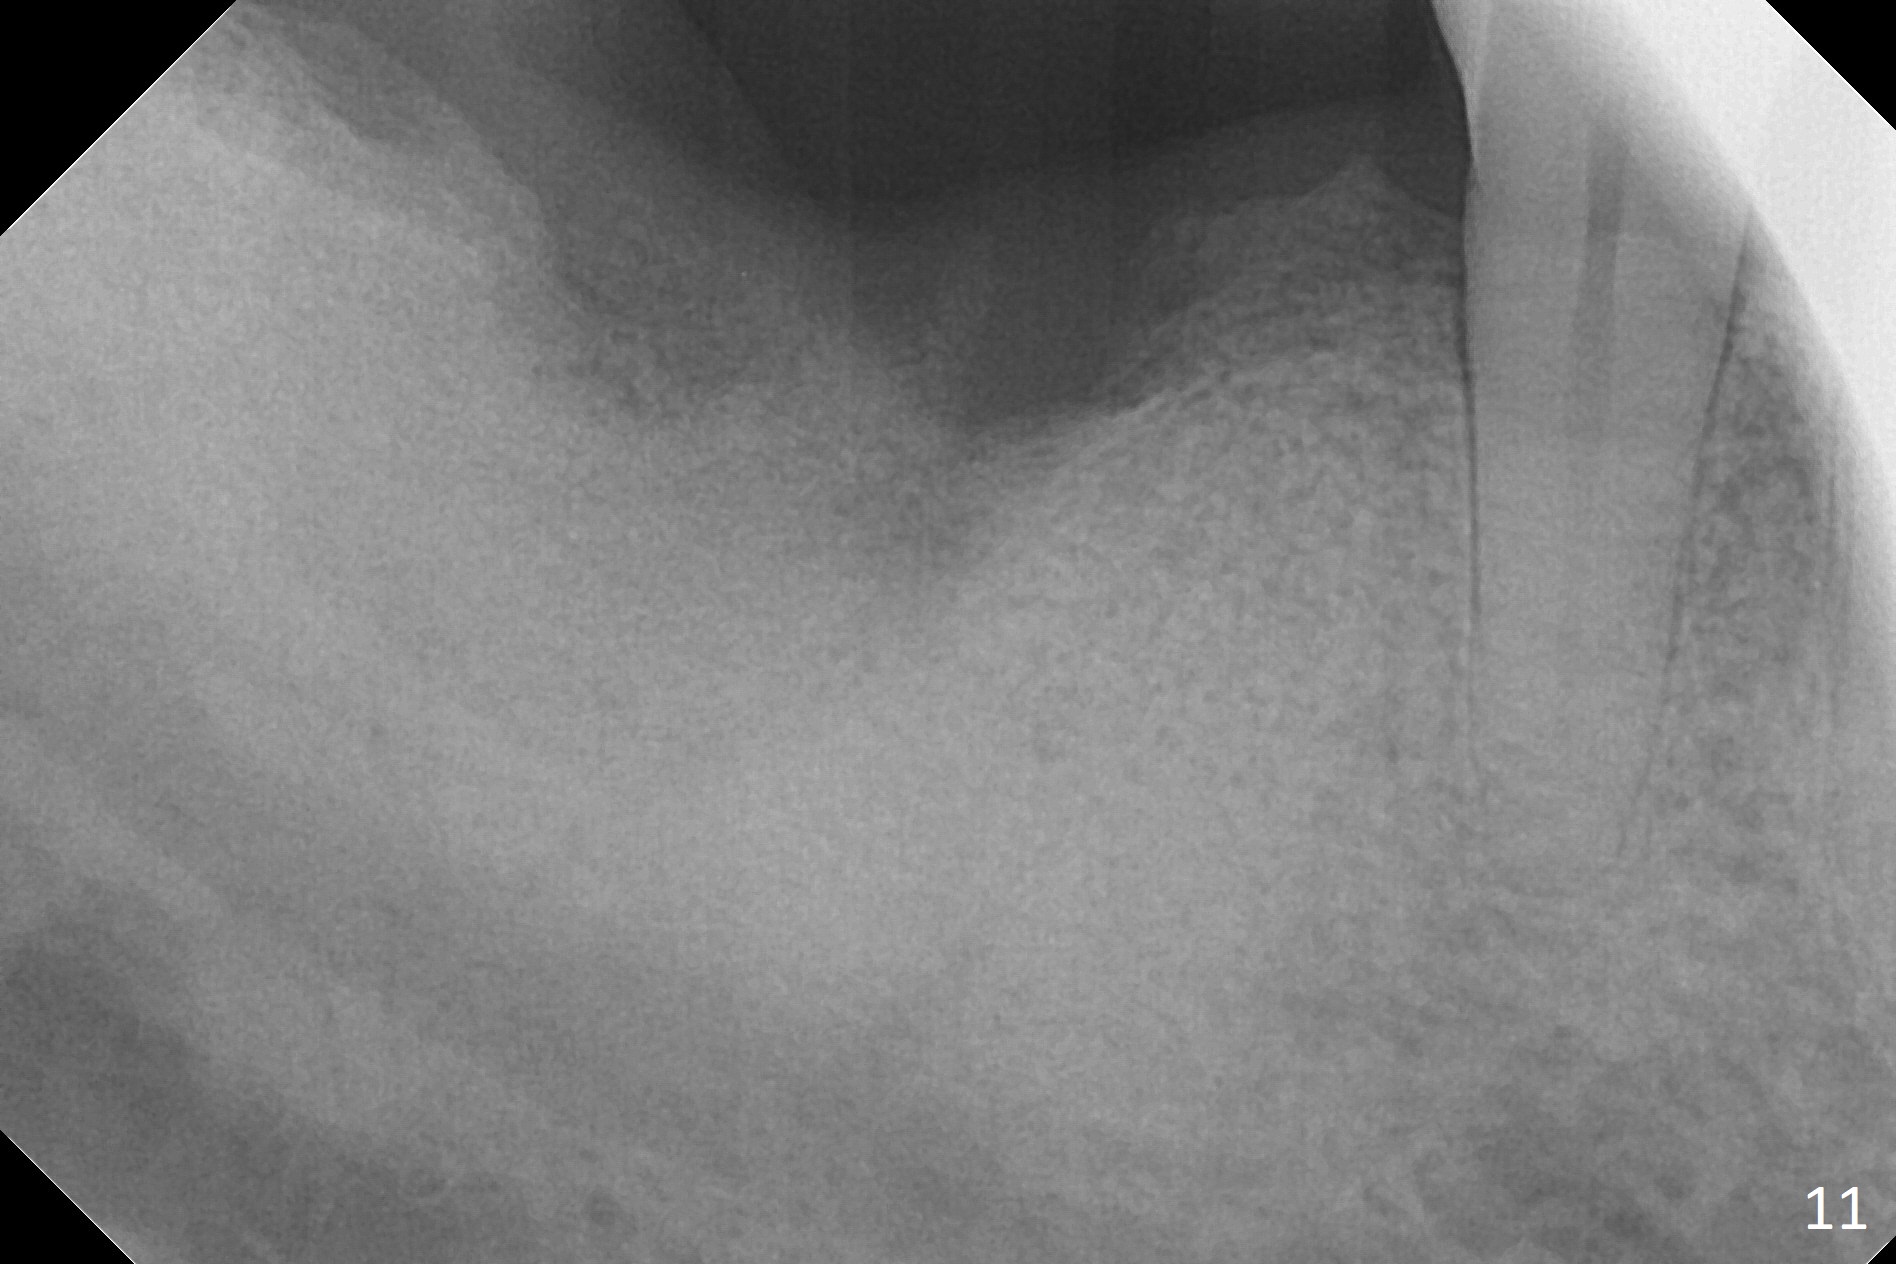

The socket heals 3 months postop (Fig.8,11). There is vertical loss of the ridge at #31 (Fig.9,10). The implant placed at #31 will be shorter than that at #30 (Fig.12). The patient will return for implant placement 4 months postop.